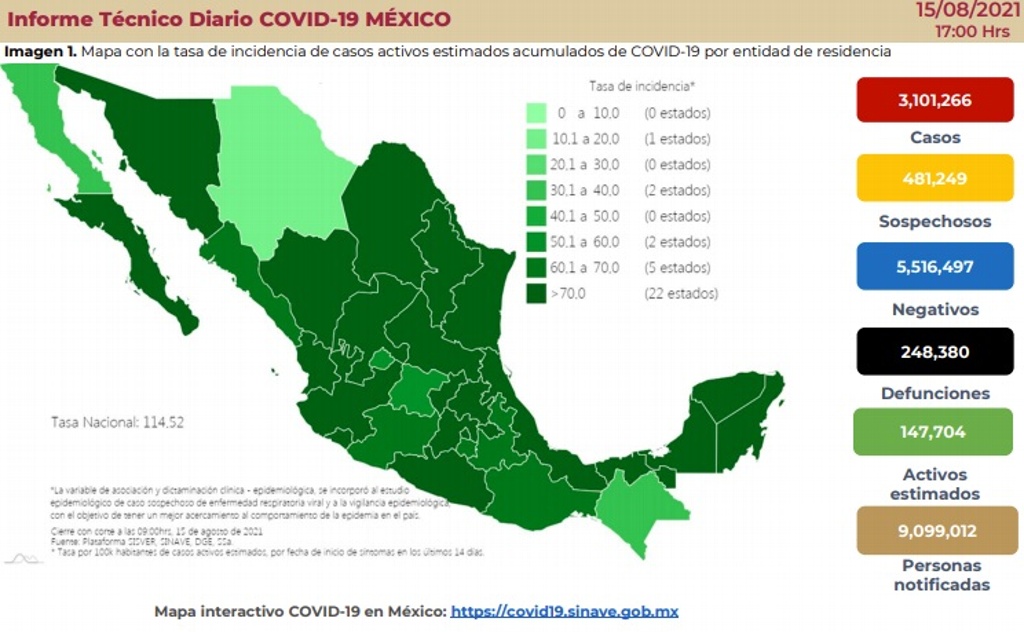

Por:xeu Noticias

El Jefe de Enfermedades Infecciosas de la Universidad de Maryland UCH, afirmó que las vacunas han actuado favorablemente frente a la variante Delta de COVID-19, ya que se reducen las muertes.

Seguir leyendo variante Delta de COVID-19, mayoría son asintomáticos: experto